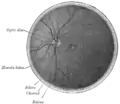

La veine centrale de la rétine draine le sang de la rétine.[réf. nécessaire]

La veine centrale de la rétine est l'équivalent veineux de l'artère centrale de la rétine. Comme ce vaisseau sanguin, il peut souffrir d'occlusion (occlusion de la veine centrale de la rétine )[4]. Cette occlusion est similaire à celle observée dans le syndrome ischémique oculaire.